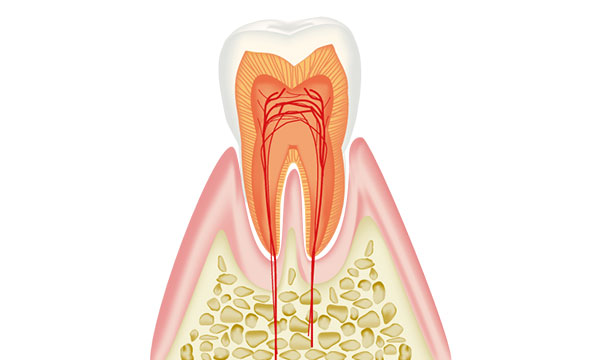

C0:虫歯の前兆

歯の表面が酸によって溶け始めるため、歯が白くなったりします。歯が虫歯で欠損する前の段階なので、フッ素を取り込んで歯ブラシをがんばれば虫歯の進行を抑える事が出来ます。 歯を削ったりする治療は必要ありません。

虫歯は進行の程度で5段階に分けられます。

歯の表面が酸によって溶け始めるため、歯が白くなったりします。歯が虫歯で欠損する前の段階なので、フッ素を取り込んで歯ブラシをがんばれば虫歯の進行を抑える事が出来ます。 歯を削ったりする治療は必要ありません。